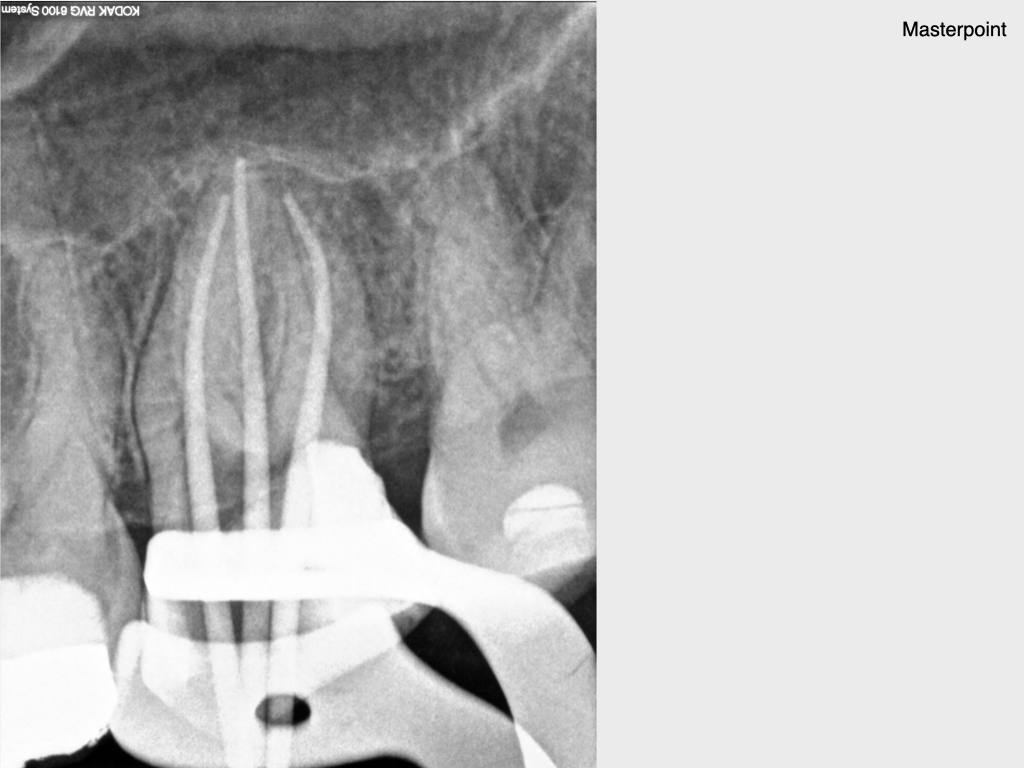

10 Jahres Recall